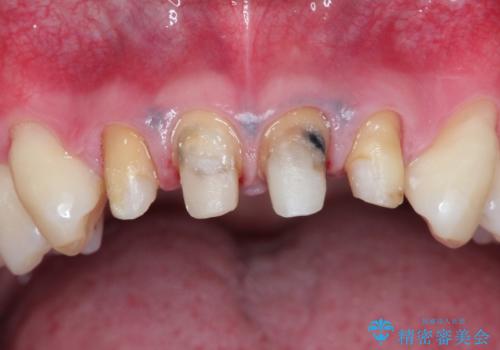

- 上の前歯の見た目が気になるとのことで来院されました。

上の前歯の4本が神経の処置がされており、前から2番目の歯が内側に入り込んでしまっていました。

また、金属で治療された根本の歯茎が黒く変色(メタルタトゥー)しており、余計に見た目がよくない状態となっておりました。

矯正治療で前歯の歯並びを整えてからセラミックほ装着する計画としました。